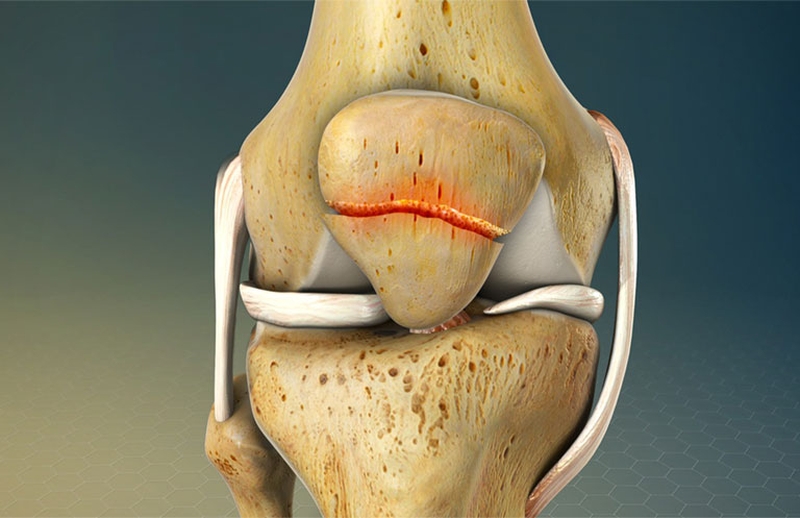

Về cơ bản, gãy xương bánh chè được phân loại thành các chấn thương ngang, dọc, gãy, rìa hoặc sụn của đầu gối.

- Gãy ngang xảy ra theo chiều ngang với xương bánh chè và thường do tác động gián tiếp lên xương bánh chè.

- Gãy dọc thường xảy ra từ cực dưới đến cực trên, ổn định và có thể được quản lý một cách bảo tồn.

- Gãy cạnh xương bánh chè xảy ra ở chu vi của xương bánh chè và thường do lực tác động trực tiếp lên mặt bên của xương bánh chè.

- Tổn thương sụn đầu gối thường gặp ở nhiều bệnh nhân, thường có liên quan đến mô mềm.

Gãy xương bánh chè được phân loại thành các chấn thương ngang, dọc, gãy, rìa hoặc sụn của đầu gối